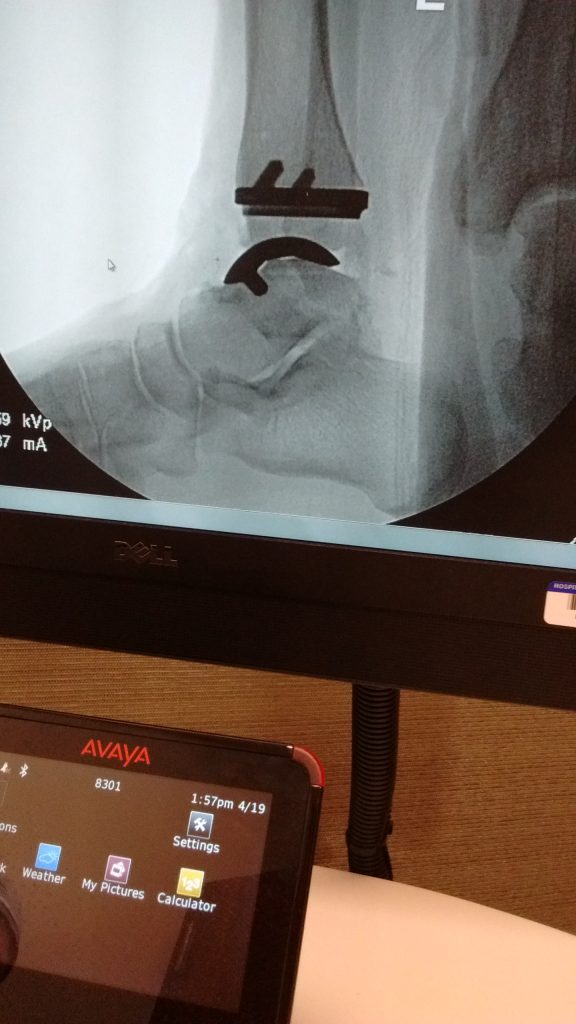

I was referred to HSS and Dr. Demetracopoulos by a surgeon who had performed my fusion two years previous because unfortunately my ankle had only fused about 30%. I met with Dr. Demetracopoulos who looked at my X-rays and felt I was a good candidate for a TAR (total ankle replacement). He explained exactly what would happen, recovery time, pain management, PT. He answered all my questions so I decided this is what I had to do. I had a CAT scan that same day, and a few weeks later had the surgery.